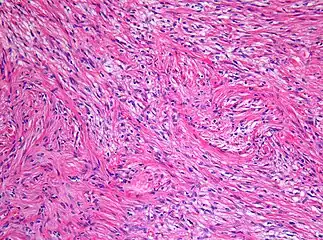

Pilocytic astrocytomas are often cystic tumors, and, if solid, tend to be well-circumscribed.

Under the microscope, the tumor is seen to be composed of bipolar cells with long "hair-like" GFAP-positive processes, giving the designation "pilocytic" (that is, made up of cells that look like fibers when viewed under a microscope[6]). Some pilocytic astrocytomas may be more fibrillary and dense in composition. The presence of Rosenthal fibers,[7] eosinophilic granular bodies, and microcysts can often be seen. Myxoid foci and oligodendroglioma-like cells may also be present, though these are not specific to pilocytic astrocytoma. Long-standing lesions may show hemosiderin-laden macrophages and calcifications.

a-c) Photomicrograph shows microcystic areas in pilocytic astrocytoma -

Histopathology of pilocytic astrocytoma (grade I WHO). -

Histopathology of Rosenthal-fibres. H&E staining showing these elongated eosinophilic structures in the case of pilocytic astrocytoma.